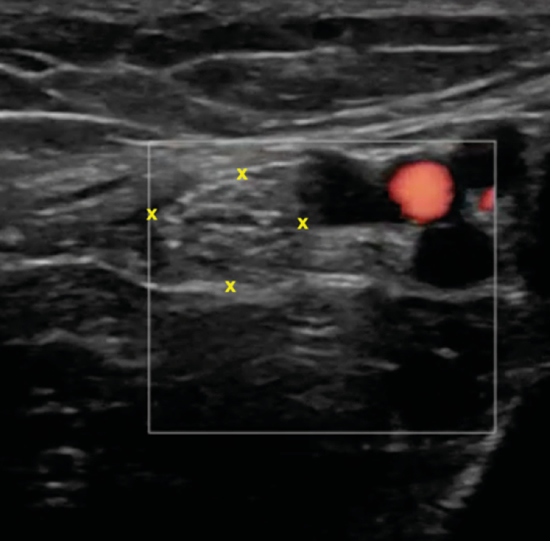

El nervio tibial, que se sitúa en superficie a las estructuras musculotendinosas y bajo la fascia crural, de forma habitual está dispuesto posterior a los vasos tibiales posteriores (Figura 6).

Figura 6. Túnel tibiocalcáneo. El examen en eje corto, bajo la fascia crural (*) y de anterior a posterior, muestra el tendón tibial posterior (TP), el tendón flexor largo de los dedos (FCD) aún con fibras musculares, y el músculo flexor largo del primer dedo (FLD). Entre estas dos estructuras se encuentra el haz neurovascular que está formado por las venas (V), la arteria (A) tibial posterior y por el nervio tibial (rodeado por X).

El nervio tibial tiene forma más o menos redondeada, patrón fibrilar con zonas punteadas anecogénicas e hiperecogénicas que corresponden a los haces nerviosos y al tejido conectivo de sostén, la típica imagen denominada de “sal y pimienta”, y sección transversal entre 10 mm26 y 12,7 mm27 a nivel del maléolo tibial (Figura 7).

Figura 7. Examen en eje corto del nervio tibial (x) posterior adyacente a los vasos tibiales posteriores.